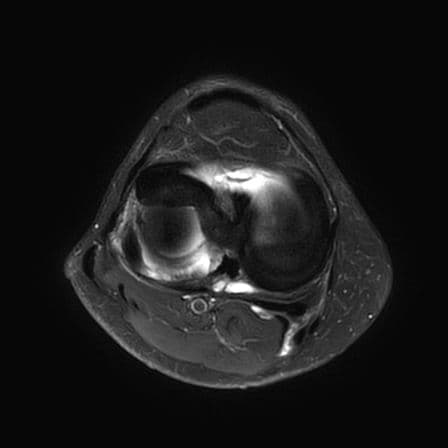

Volumineuse lésion en anse de seau du ménisque latéral avec luxation du fragment méniscal sur le profil antérieur de l'échancrure inter-condylienne, conservation de l'attache méniscale antérieure, l'attache méniscale postérieure apparaît rompu.